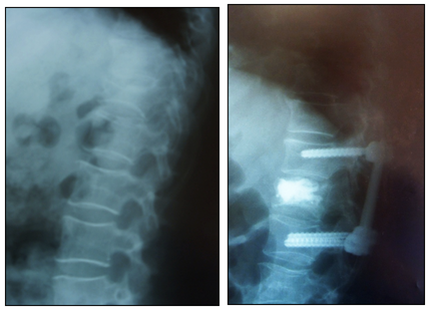

Таким образом, возможно более широкое применение перкутанной ТПФ у пациентов с высокой степенью операционного риска, в том числе в старшей возрастной группе. При лечении этих пациентов сохранение функции мышечного аппарата, может быть, даже более важно, чем у молодых пациентов, у которых есть резервы восстановления. Однако, применение металлоконструкций у пациентов с остеопоротическими изменениями сопряжено с проблемами фиксации импланта в кости. Сочетание перкутанной ТПФ с вертебропластикой и кифопластикой тел позвонков, аугментацией винтов позволяет решить данную проблему (Рис 7, 8) [11].

Рис. 7. Перкутанная ТПФ и вертебропластика L-I позвонка.

Рис. 8. Перкутанная ТПФ с аугментацией винтов и вертебропластика Th-ХI позвонка.